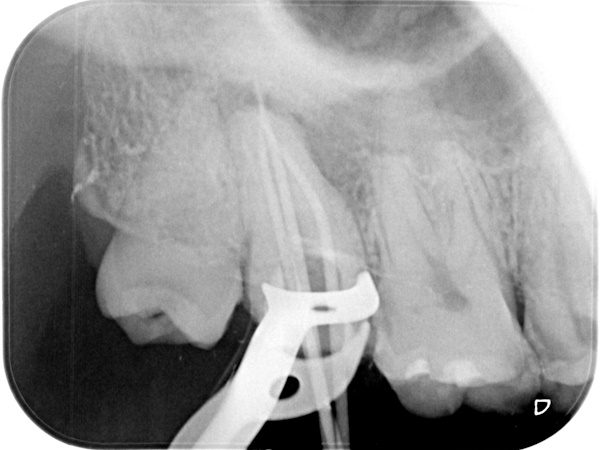

【 上の歯の精密根管治療 】

術前から術後までの治療の流れ

根管治療中(試適時)